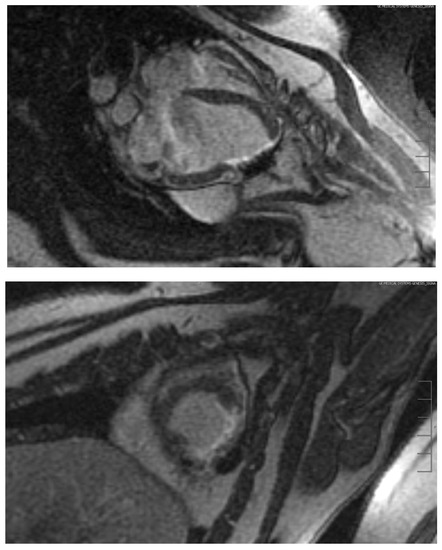

Figure 6. Cardio MRI three months following the reconstruction of the myocardium with an autologous vascularised gastric patch and stabilisation with a degradable magnesium scaffold. Top: Cine steady-state free precession (SSFP) in short axis from midventricular to apex cordis. Bottom: Cine SSFP with left ventricular two-chamber view. Good integration of the transplanted gastric patch.

Figure 7. Cardio MRI with delayed enhancement imaging 6 months following the reconstruction of the myocardium with an autologous vascularised gastric patch, and stabilisation with a degradable magnesium scaffold. Top: Four-chamber view with evidence of a significant ribbon-like late enhancement from apex cordis until the middle of the left ventricle, indicating fibrotic remodelling in the border zone between the myocardium and the transplanted gastric patch.

Before euthanasia, the test animals were examined by a cardiac MRI to determine the volume and functional data of the left ventricle. Stable integration of the stomach patch through adjacent scar tissue could be detected already after three months following implantation (Figure 6). The late enhancement of the contrast medium in this tissue area was a clear indication of fibrotic remodelling processes (Figure 7). All the animals without aneurysm formation showed normal left ventricular volume values as well as normal left ventricular ejection fractions. However, reduced motility of the ventricular wall in the junction area between the cardiac muscle and graft could be observed in all animals.

Three animals featured aneurysmal outpouching in varying degrees of severity in the area of the transplanted stomach tissue. The animal with the largest aneurysm in the area of the transplanted stomach tissue showed a significant increase in its end-diastolic and end-systolic volume, a significant reduction in stroke volume, and consecutively a significant decrease in the left ventricular ejection fraction to 36.4%. The animal that had developed the smallest aneurysm with a volume of only 6.8 mL showed no reduction in its left ventricular pump function (LV-EF 61.8%).